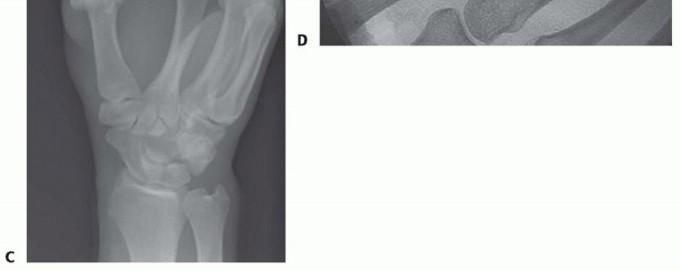

TECH FIG 5 • Tension band wire technique of arthrodesis in AP (A) and lateral (B) projections. Note the presence of the two parallel Kirschner wires, bent over at ends, and the stainless steel wire figure-8 construct.